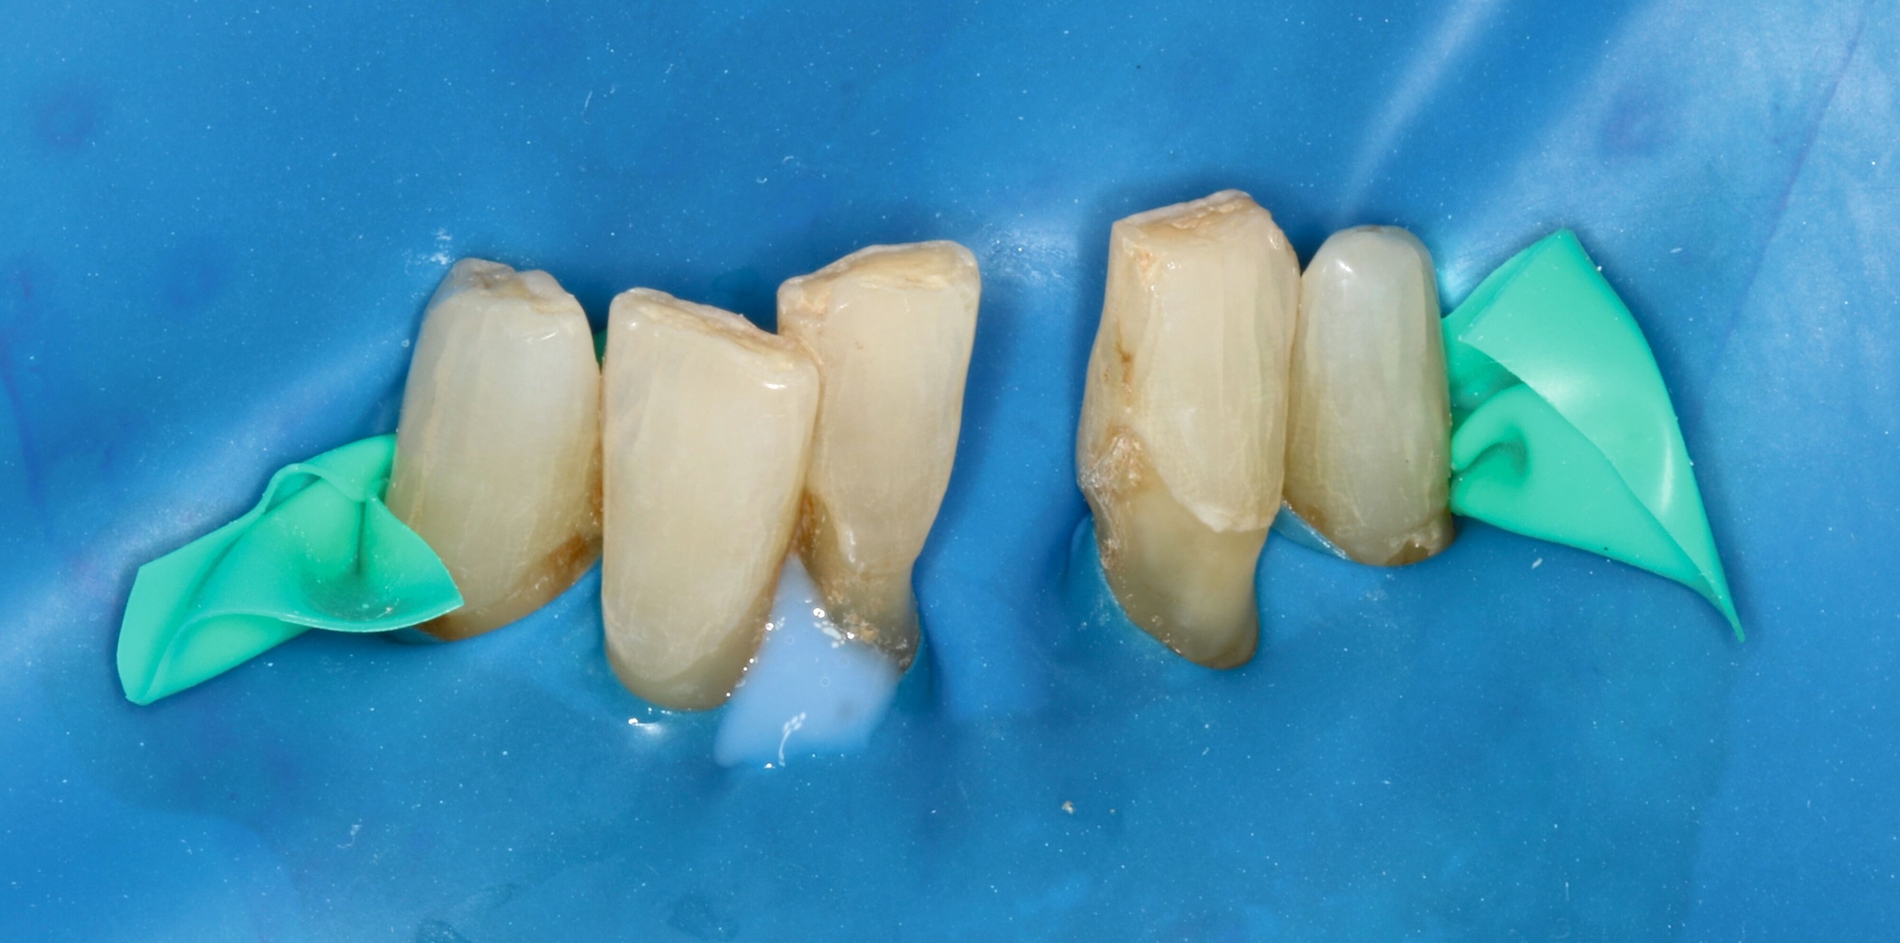

Um bei der adhäsiven Befestigung des Kunststoff-Prothesenzahns das Risiko einer Speichelkontaminierung zu reduzieren, wurde Kofferdam verwendet. Die Interdentalräume wurden mit einer elastischen Befestigungsschnur (Wedjets, Coltene) blockiert, um ein späteres Ausfließen der Interdentalräume mit Komposit zu verhindern – einerseits um weiterhin eine gute häusliche Mundhygiene zu ermöglichen, andererseits um keine unnötig langwierige Nacharbeitung bei der Entfernung von überschüssigem Komposit zu verursachen (Abbildung 9).

Anschließend wurde die unpräparierte Zahnoberfläche mittels 35-prozentiger Phosphorsäure (Ultra Etch, Ultradent) 60 Sekunden lang geätzt, mit einem Zwei-Komponenten-Adhäsivsystem (Optibond FL, Kerr) vorbereitet und das zur Schienung verwendete Polyethylenband (Ribbond THM Adhäsiv Verstärkungsband, Ribbond Inc.) mit Komposit (CeramX Spectra STHV & ST flow, Dentsply Sirona) fixiert. Die Polyethylenband-Oberfläche wurde großzügig mit Komposit überdeckt, ebenso wurden die Zähne mittels Komposit deutlich verblockt, um eine möglichst hohe Stabilität der Schienung zu erreichen. Gleichzeitig wurde weiterhin darauf geachtet, dass die Hygienefähigkeit der Interdentalräume erhalten bleibt (Abbildung 10).